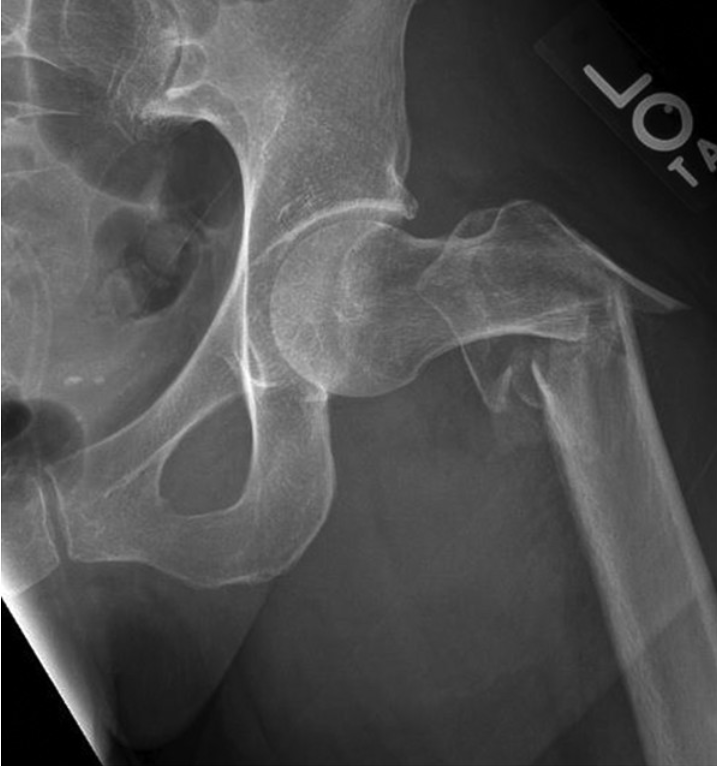

股骨颈内包含抗压与抗拉骨小梁,它们围成Ward三角。该三角上界为抗拉骨小梁,内下界为抗压骨小梁,是骨密度较低的区域(图1)。近期研究表明,骨小梁退化与股骨颈骨折发生密切相关,而Ward三角扩大则与股骨粗隆间骨折相关。

图1. (左)一位30岁女性患者的右髋X光片。(右)一位98岁男性患者的右髋X光片。注意右图中Ward三角(WT)的大小明显大于左图,并且与左图相比,右图中主要抗压骨小梁(A)和主要抗拉骨小梁(B)的退变更明显。